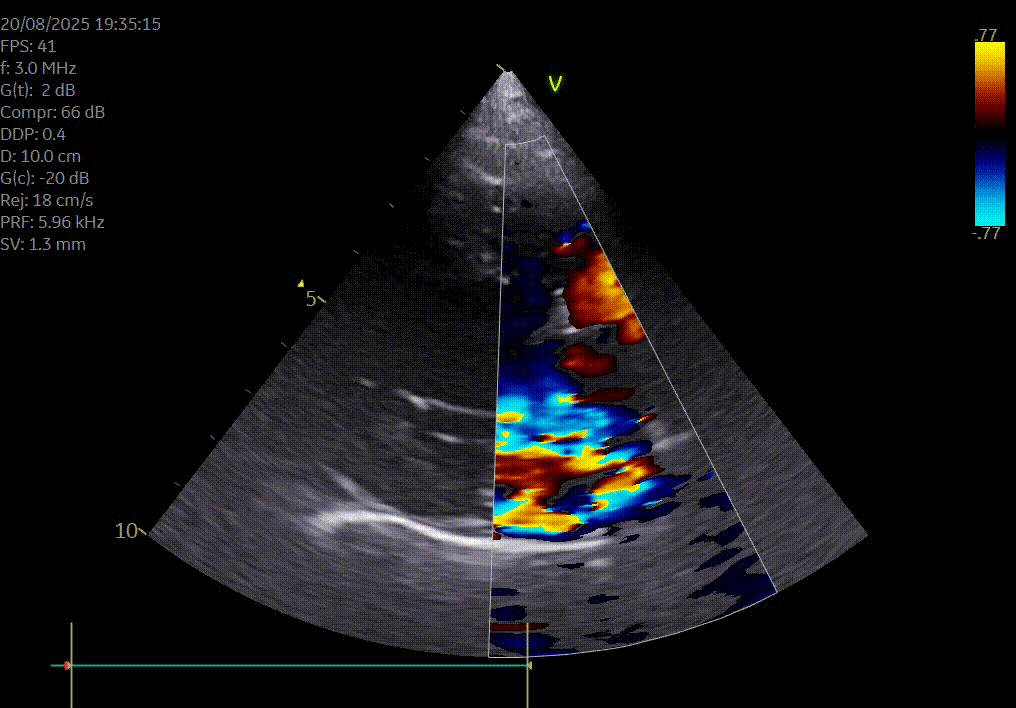

Heeft uw hond of kat een hartruis? Het is dan aangewezen om een echocardiografie (hartfilmpje) uit te laten voeren om na te gaan of er best ondersteunende hartmedicatie moet opgestart worden. Met een echocardiografie gaan we na of het hart normaal gevormd is, normaal werkt en beoordelen we de ergheidsgraad van eventuele kleplekken.

Hartonderzoek - Echocardiografie - Electrocardiografie (EKG) - Radiografie